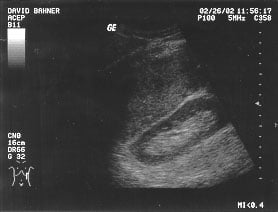

Cardiac - Subxiphoid view (unlabeled)